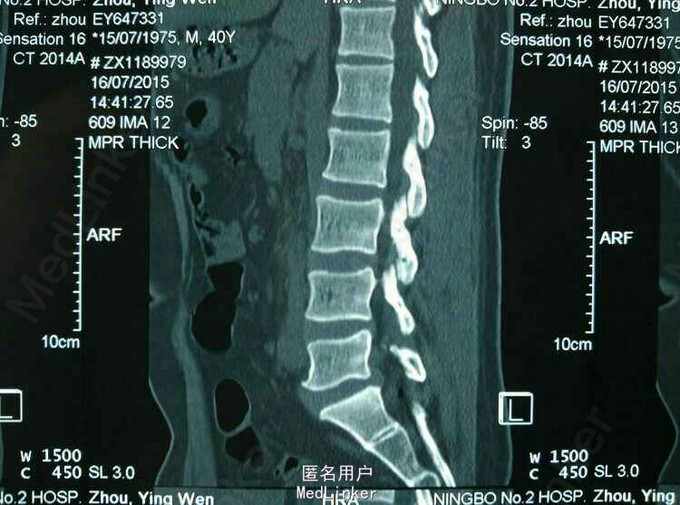

MRI及CT:L5S1 椎间盘脱出,向上游离。

诊断:L5S1椎间盘脱出(向上高度游离) 治疗:后路经椎板间入路椎间孔镜下髓核摘除,射频消融。